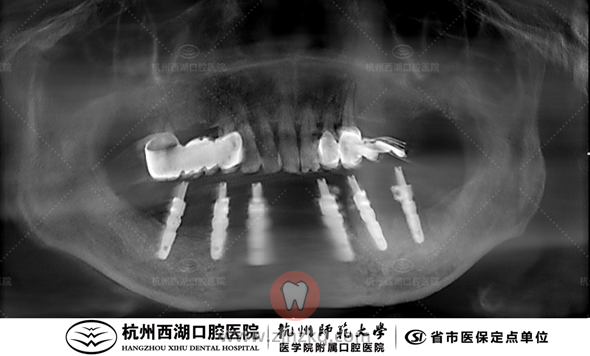

医生建议:下颌拔除,All-on-6即刻负重

术前CBCT照如下

种植团队采用All-on-6即刻修复技术,为宋叔叔植入6颗种植体,即日戴牙完成半口修复。